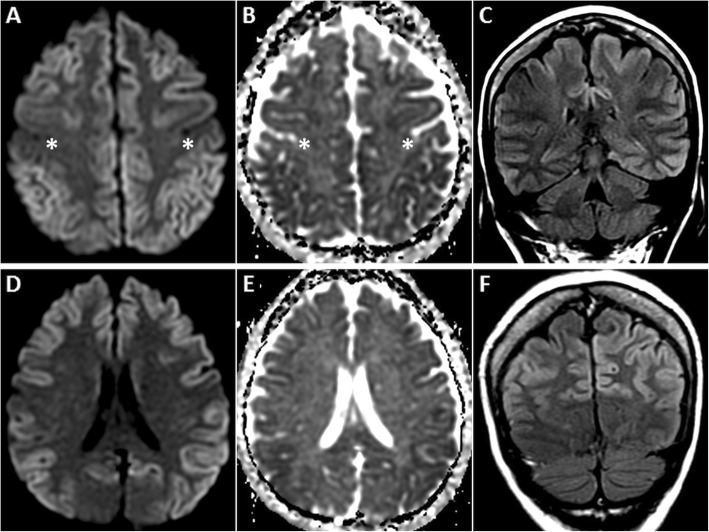

Fig. 9.

MRI of the brain in a 58-year-old female patient who presented with rapidly progressive dementia due to sCJD. Symmetric GRD is seen in the cerebral cortices on axial DWI (a, d) and ADC images (b, d, e) with sparing of the perirolandic regions (asterisks in a, b). Coronal FLAIR images (c, f) shows hyperintense signal in the affected cortices